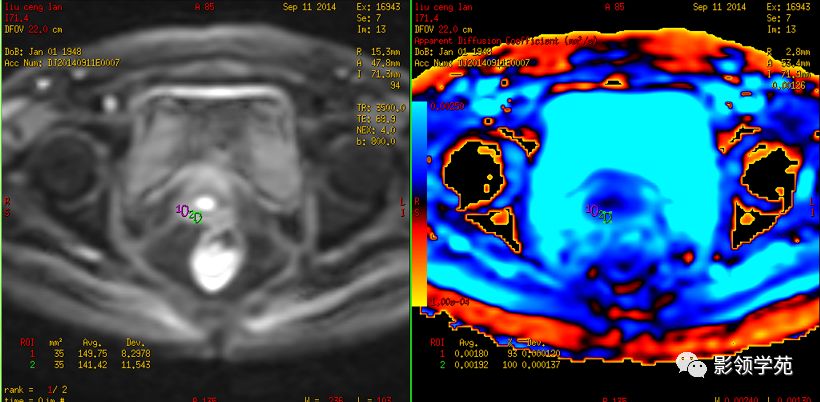

磁共振扩散加权成像,DWI

DWI是目前唯一能在活体观察组织水分子微观运动的无创性影像学方法,可以检测出与组织含水量变化相关的形态学和生理学早期改变,并以表观扩散系数(ADC)值来量化表示。

DWI在宫颈癌中的应用

DWI:局限性高信号,癌组织ADC值<癌旁组织<小于正常宫颈组织

宫颈癌术后复发患者,DWI上病灶较T2 fs及T1+C更加明显

DWI显示淋巴结肿大